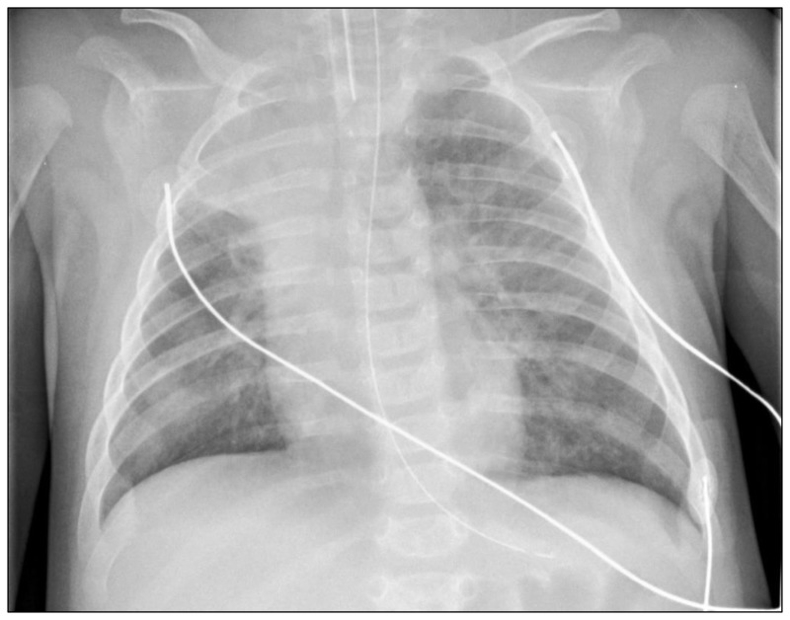

- Chest X-Ray:

- Hyperinflation (air trapping)

- Peribronchial thickening

- Atelectasis

- Increased linear markings